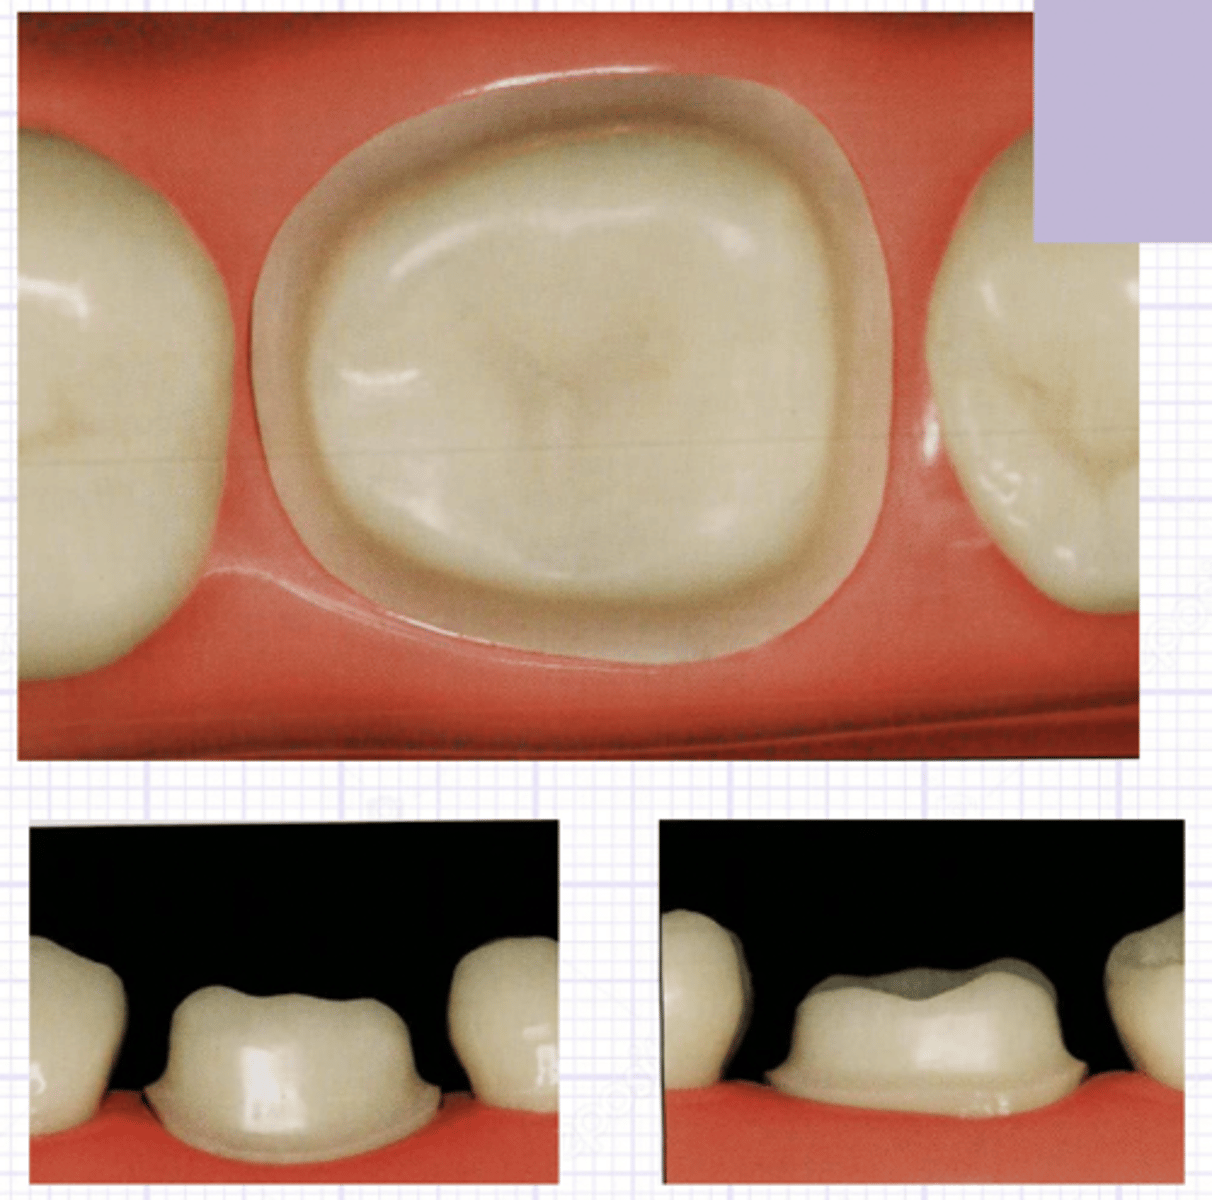

symmetrical

composite

all porcelain crown

veneer